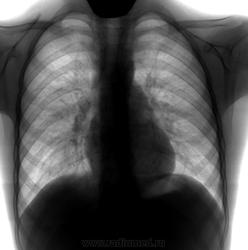

Опять "о. бронхит". 8-9лет, м."Хрипов нет", Т до 38. Жалобы на слабость и все. Тут уж рентгенолог не искл. пневмонию, " слева и справа? в н/доле?" А Ваше мнение?

Правый бок доснять, мне средние отделы совсем не нравятся.

И мне тоже. Но до пневмонии как-то не дотягивает. Пока.

Пневмония справа - на первом месте. Нужен правый бок.

Миргалина дело говорит.В прикорневых зонах с обеих сторон напряжёнка.

Соглашусь с Дмитрием, что справа в среднем поле была пневмония. Считаю, динамику положительной.А нормализация рентгеновской картины может и через месяц только наступить.Но можно и у фтизиатра проконсультировать, коль есть сомнения. Пусть свои пробы ставит.